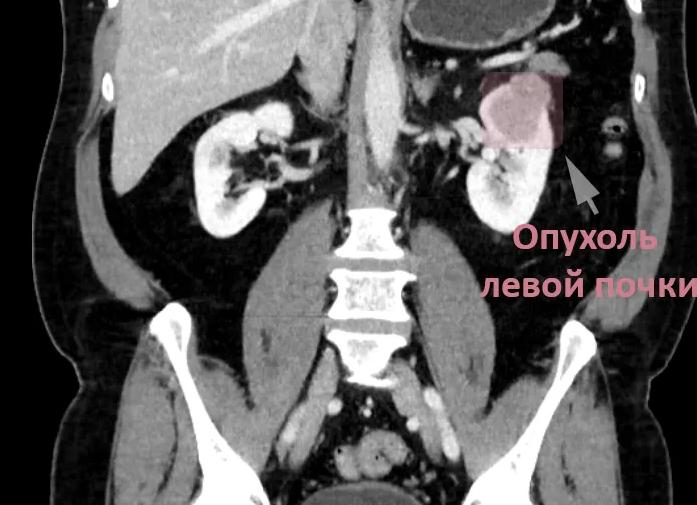

Новообразование на снимке обычно выделяется отличным от других тканей цветом, из-за разной плотности. К примеру, киста имеет плотность меньшую и образует чёткие контуры. Раковые клетки формируются неоднородно и выглядят размытыми.

Если при КТ обнаружено новообразование, то на экране оно будет выделено другим оттенком, так как имеет плотность несколько иную, отличную от плотности почки. Например, киста по плотности ниже и имеет чёткие границы, а раковые опухоли очерчены не так чётко, а их структура неоднородна. Если при сканировании почек или надпочечников используется контраст, то опухолевидные образования большого объёма становятся более плотными, чем киста, но менее, чем здоровые ткани почки. Если в области надпочечников обнаружены опухоли сосудов, то после применения контрастирующего вещества они станут чётко различимы на экране.